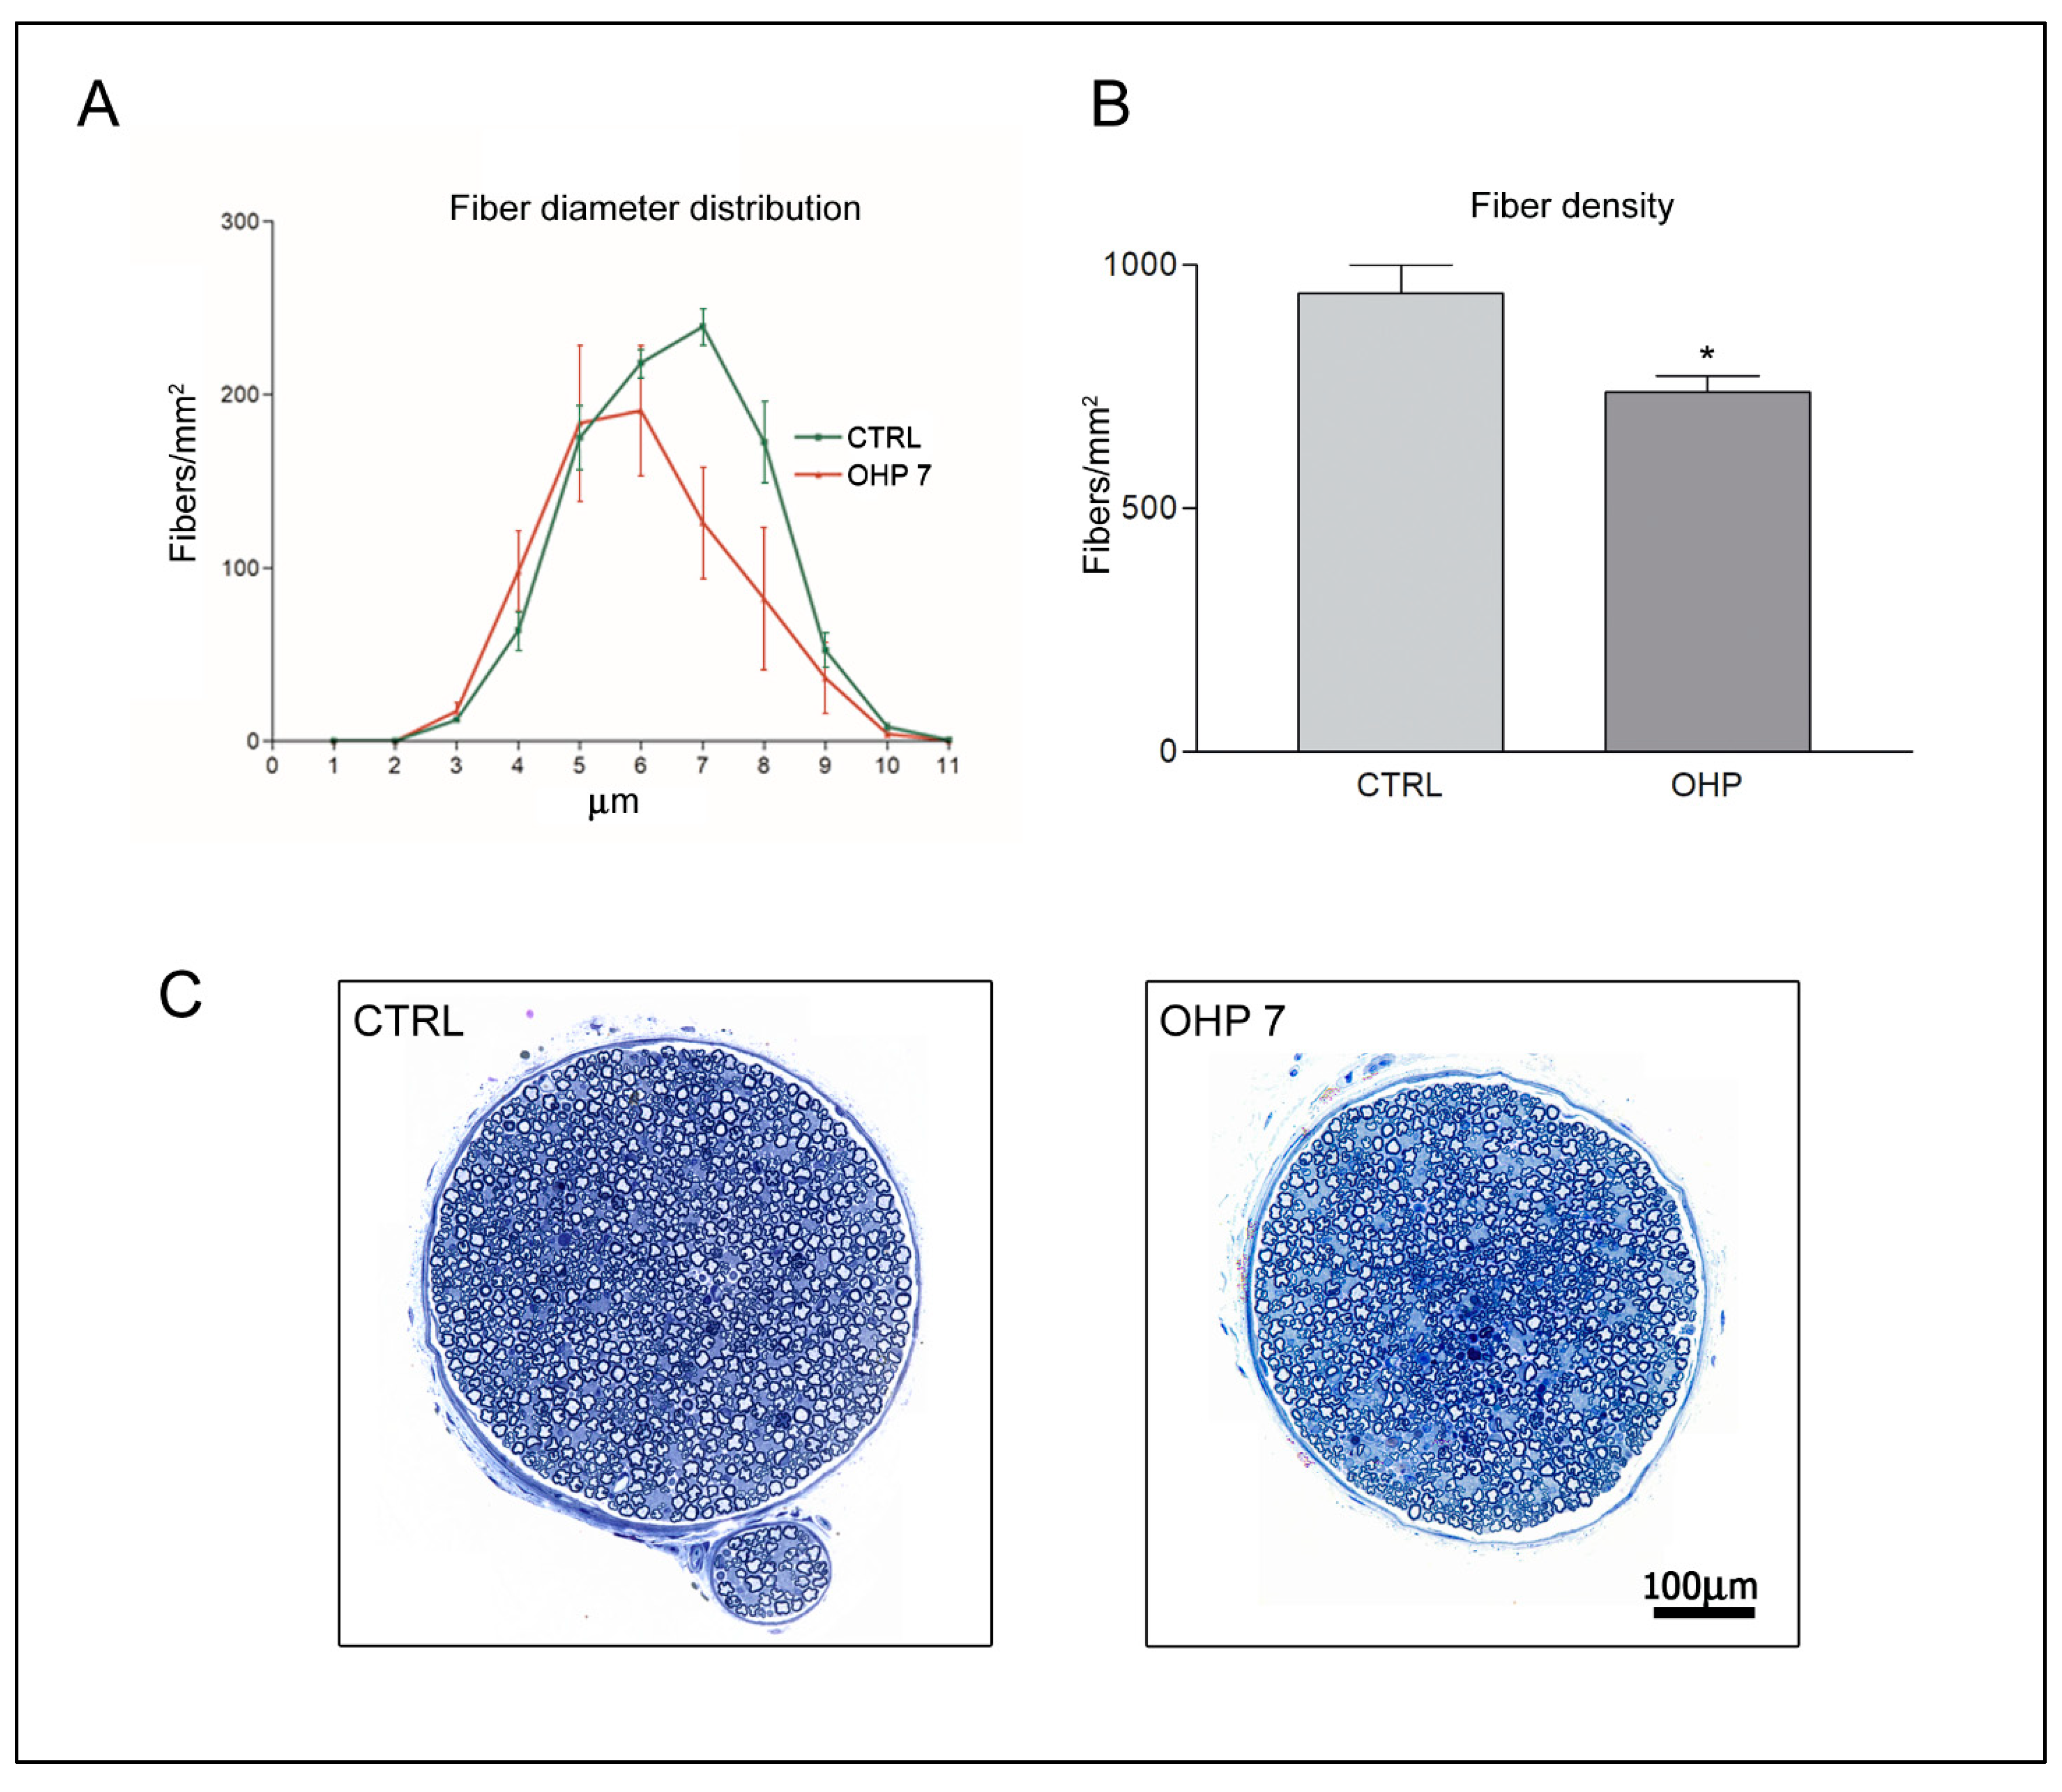

2.2.3. Caudal Nerve Morphology and Morphometry

4.2.5. Caudal Nerve Morphology and Morphometry